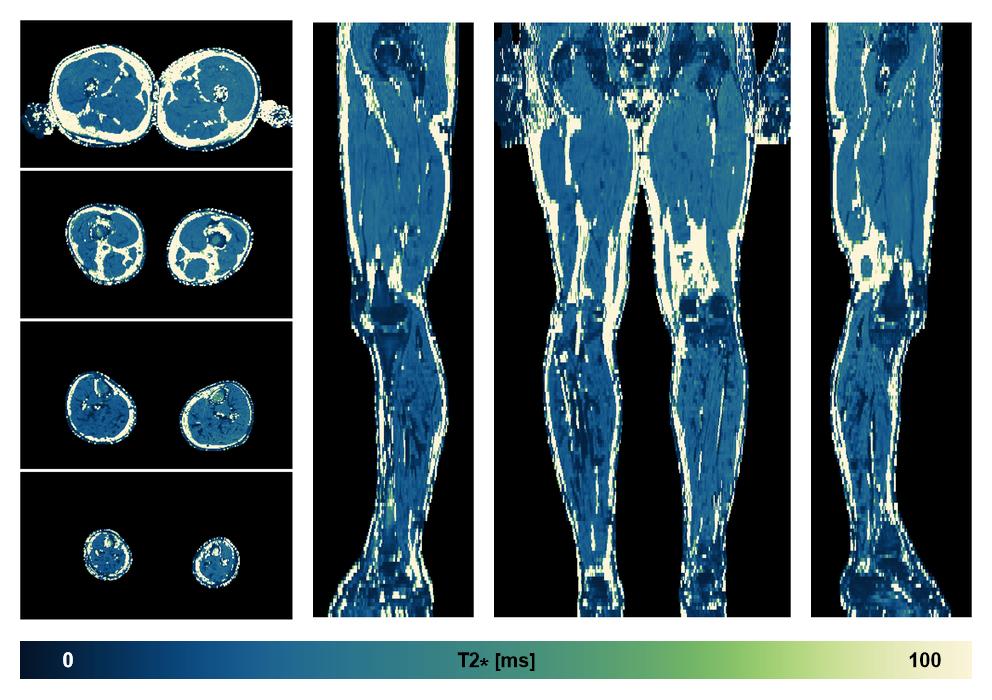

• R2 star relaxation

The R2 star relaxation time of the lower extremity obtained from the dixon reconstruction for muscle water fat quantification.